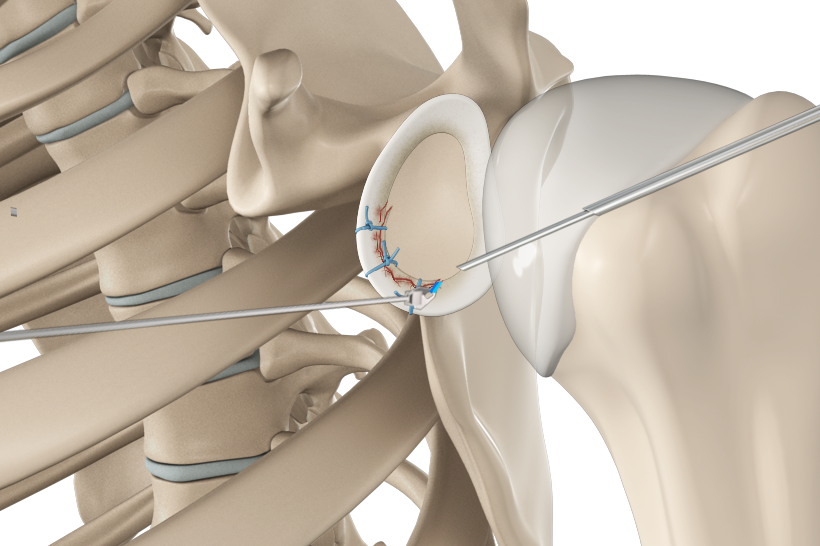

SLAP Repair

A SLAP repair is an arthroscopic shoulder procedure to treat a specific type of injury to the labrum called a SLAP tear.

Arthroscopic Bankart Repair

The labrum can sometimes tear during a shoulder injury. A specific type of labral tear that occurs when the shoulder dislocates is called a Bankart tear.